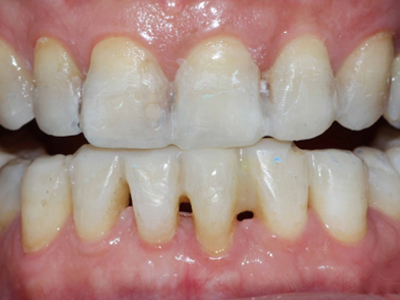

牙龈退缩露出淡黄色牙根图

牙龈退缩患者的牙龈退缩后,淡黄色牙龈明显露出。若进一步发展,易使对应位点的牙槽骨发生骨吸收,可能诱发龋齿、牙龈敏感、菌斑堆积等。